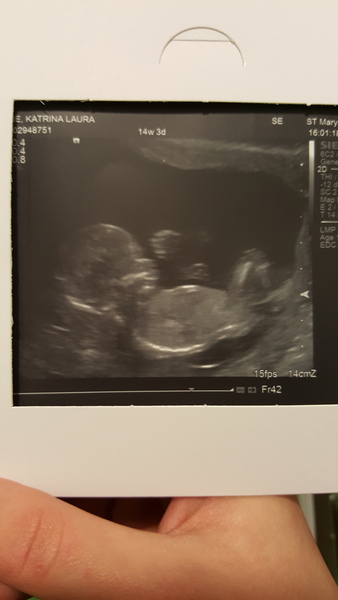

Hey everyone scan went fine they can't find resonance for pain so not much of an explanation but glad baby is okay very active 14+3 x

Wanting that's great news that all ok! So pleased! What a cutie on the scan pic too.